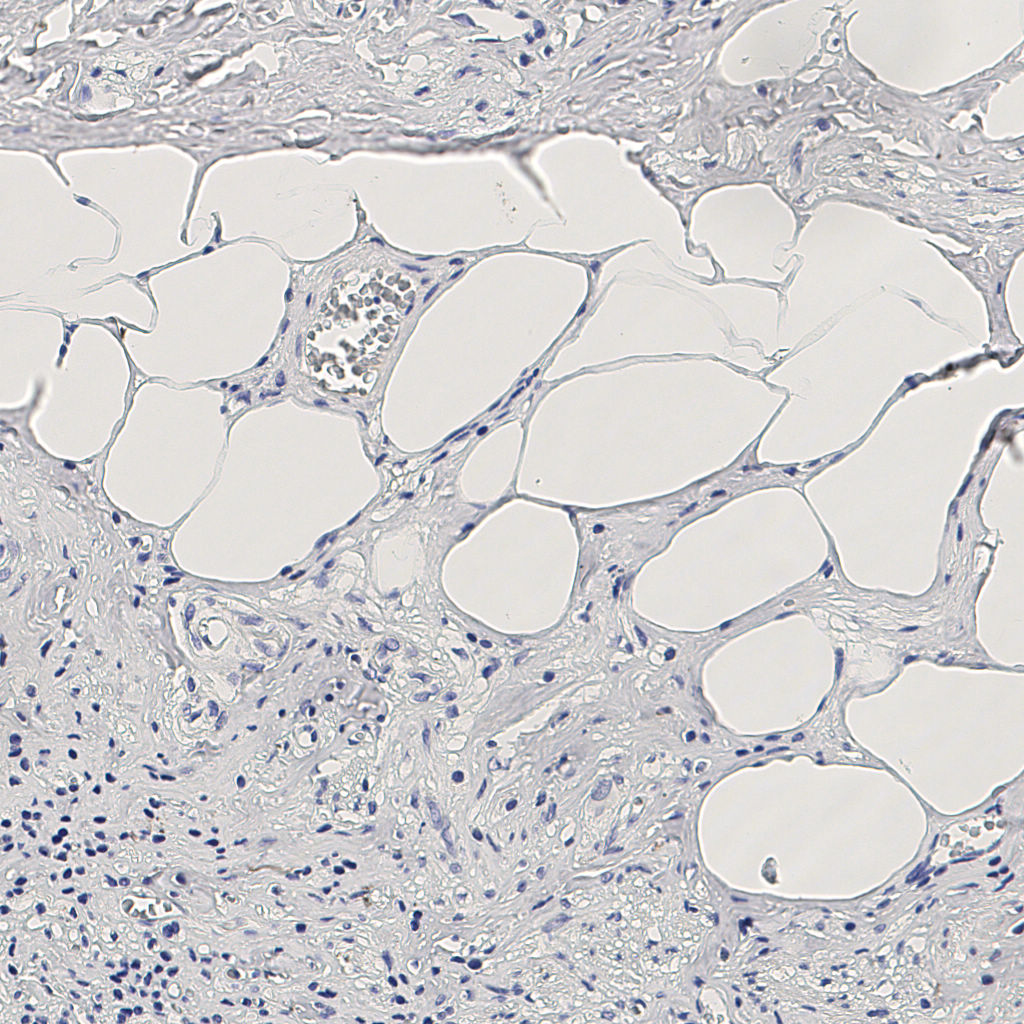

7.85%

Ki67 指数

阴 1104 阳 94

H255858-KI-67.ndpi

slice_9_20_x8064_y17920.png